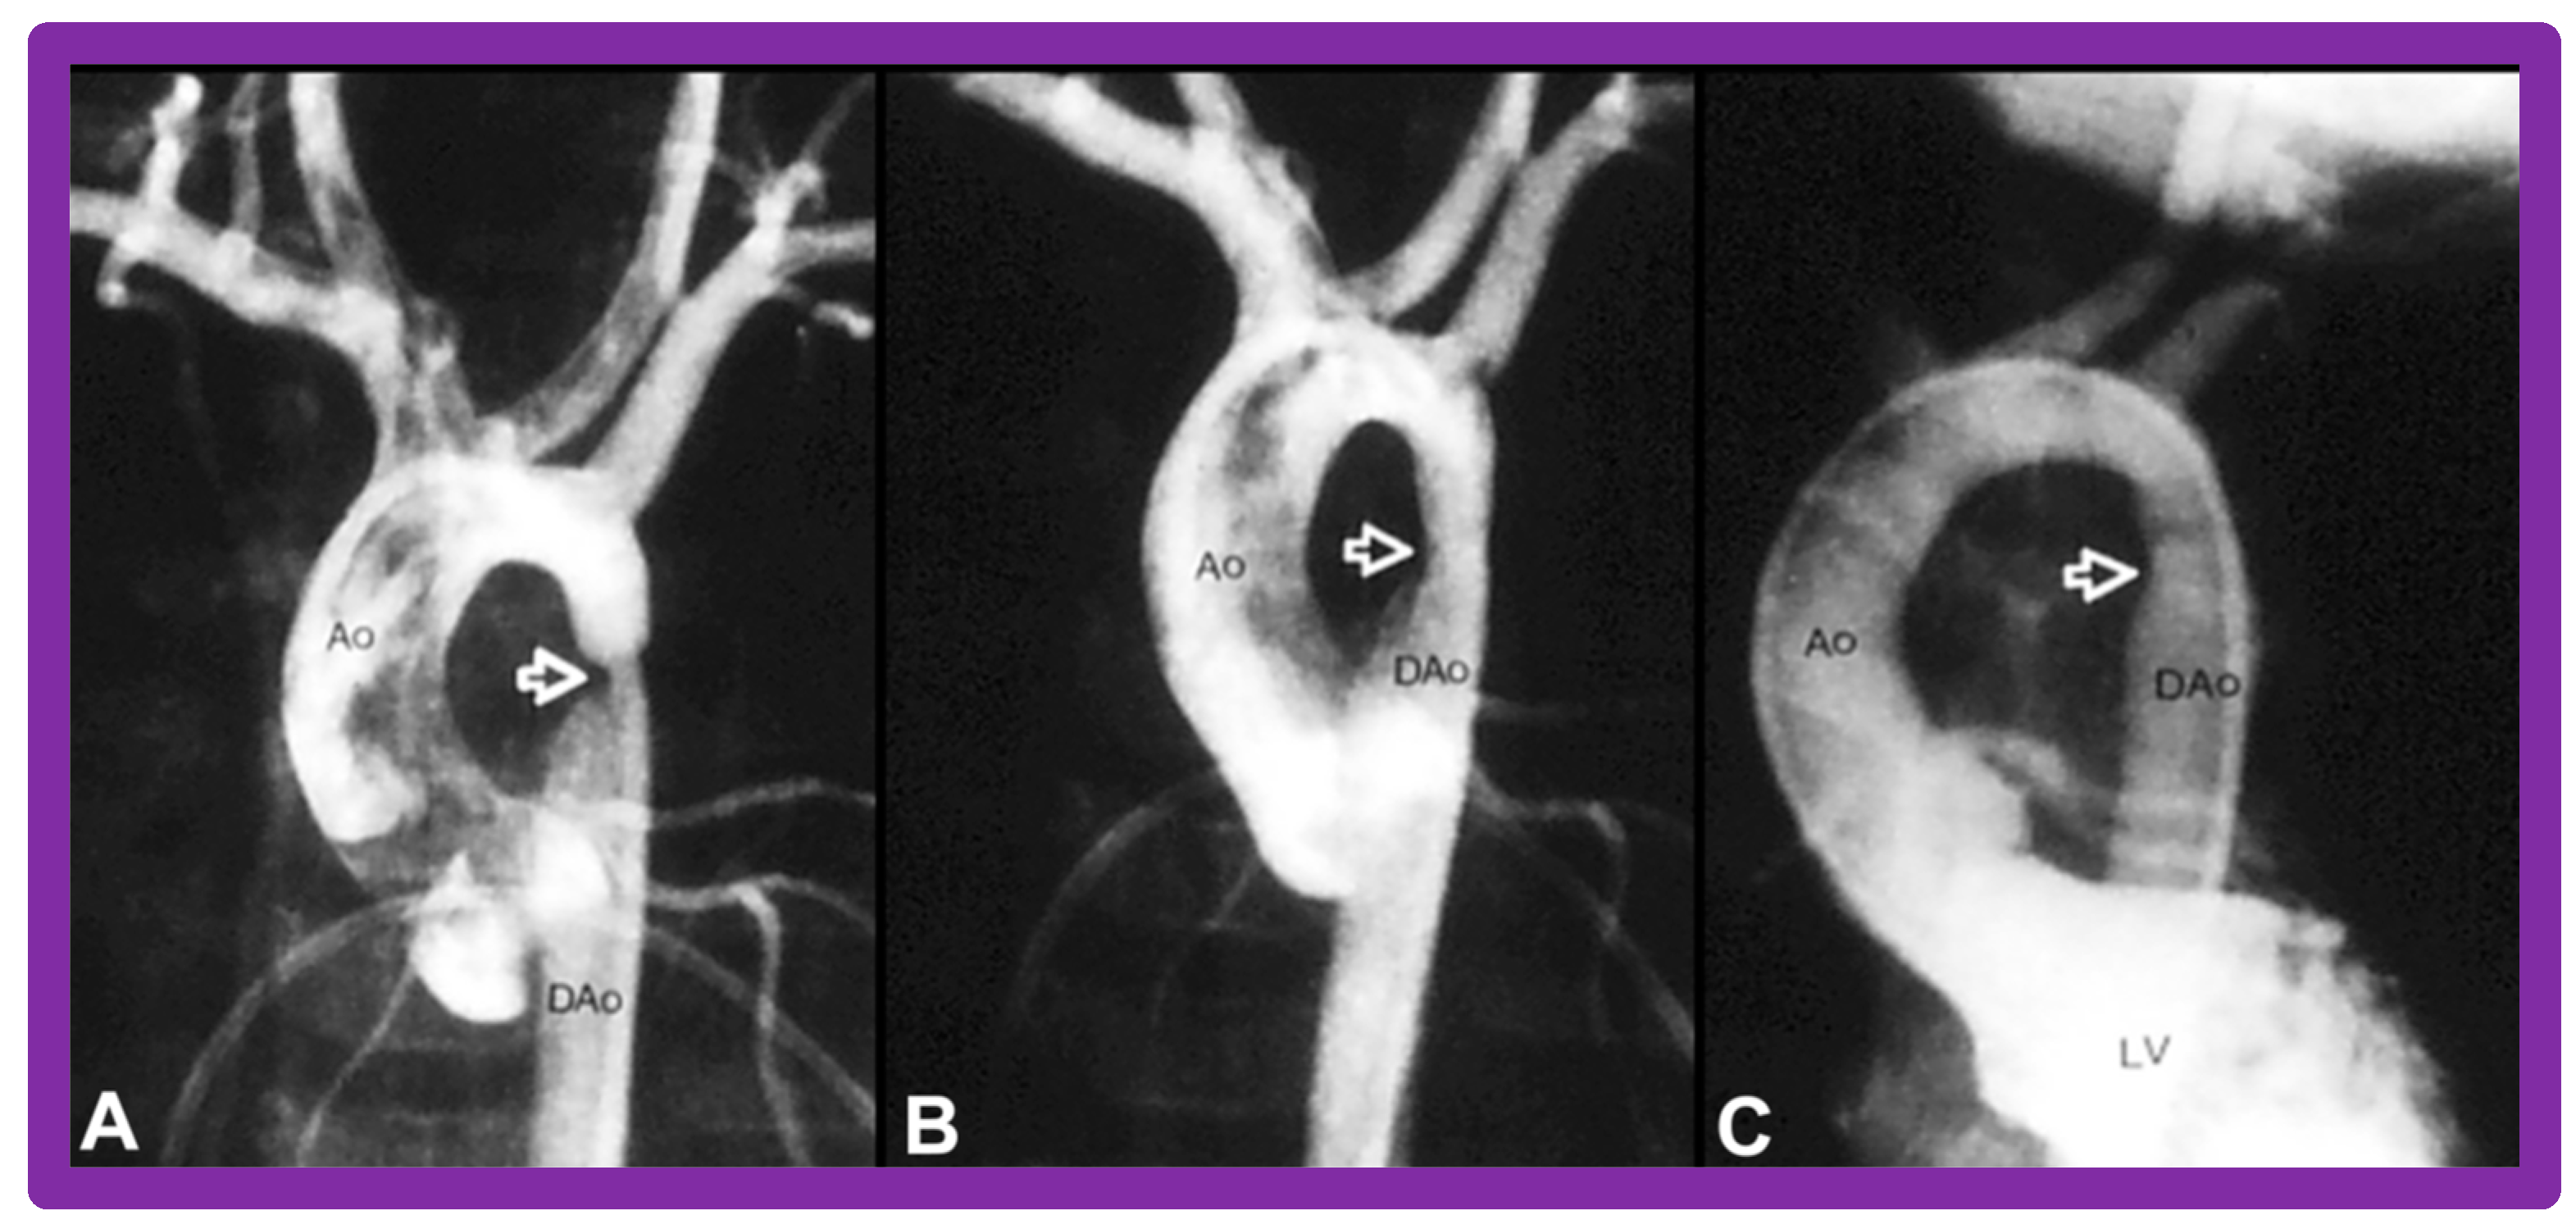

3.3. Aortic Coarctation, Native

4.3. Aortic Coarctation–Native

5.3. Aortic Coarctation–Native

5.3.1. Causes of Restenosis

5.3.2. Feasibility of Repeat BA to Address Recurrence of AC